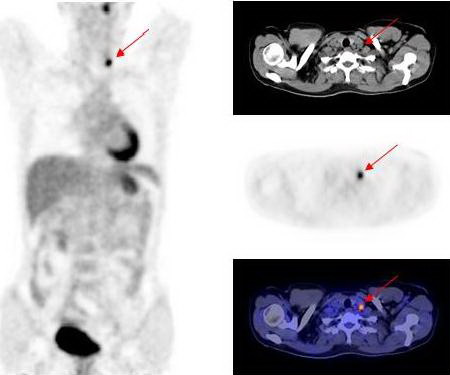

Hình 3: Hình ảnh PET/CT cho thấy tổn thương di căn hạch cổ trái.

Hình 4: Hình ảnh di căn hạch thượng đòn trái

Kết quả PET/CT: tổn thương tăng hấp thu FDG mạnh tại vòm họng bên trái, max SUV=11,8, các tổn thương di căn hạch tại vùng cổ bên phải và bên trái.

Dựa vào các kết quả trên, bệnh nhân được chẩn đoán là ung thư vòm họng di căn hạch cổ hai bên. Đồng thời đánh giá được giai đoạn bệnh của bệnh nhân là T1N2M0, kế hoạch điều trị tiếp theo là xạ trị phối hợp hoá trị.